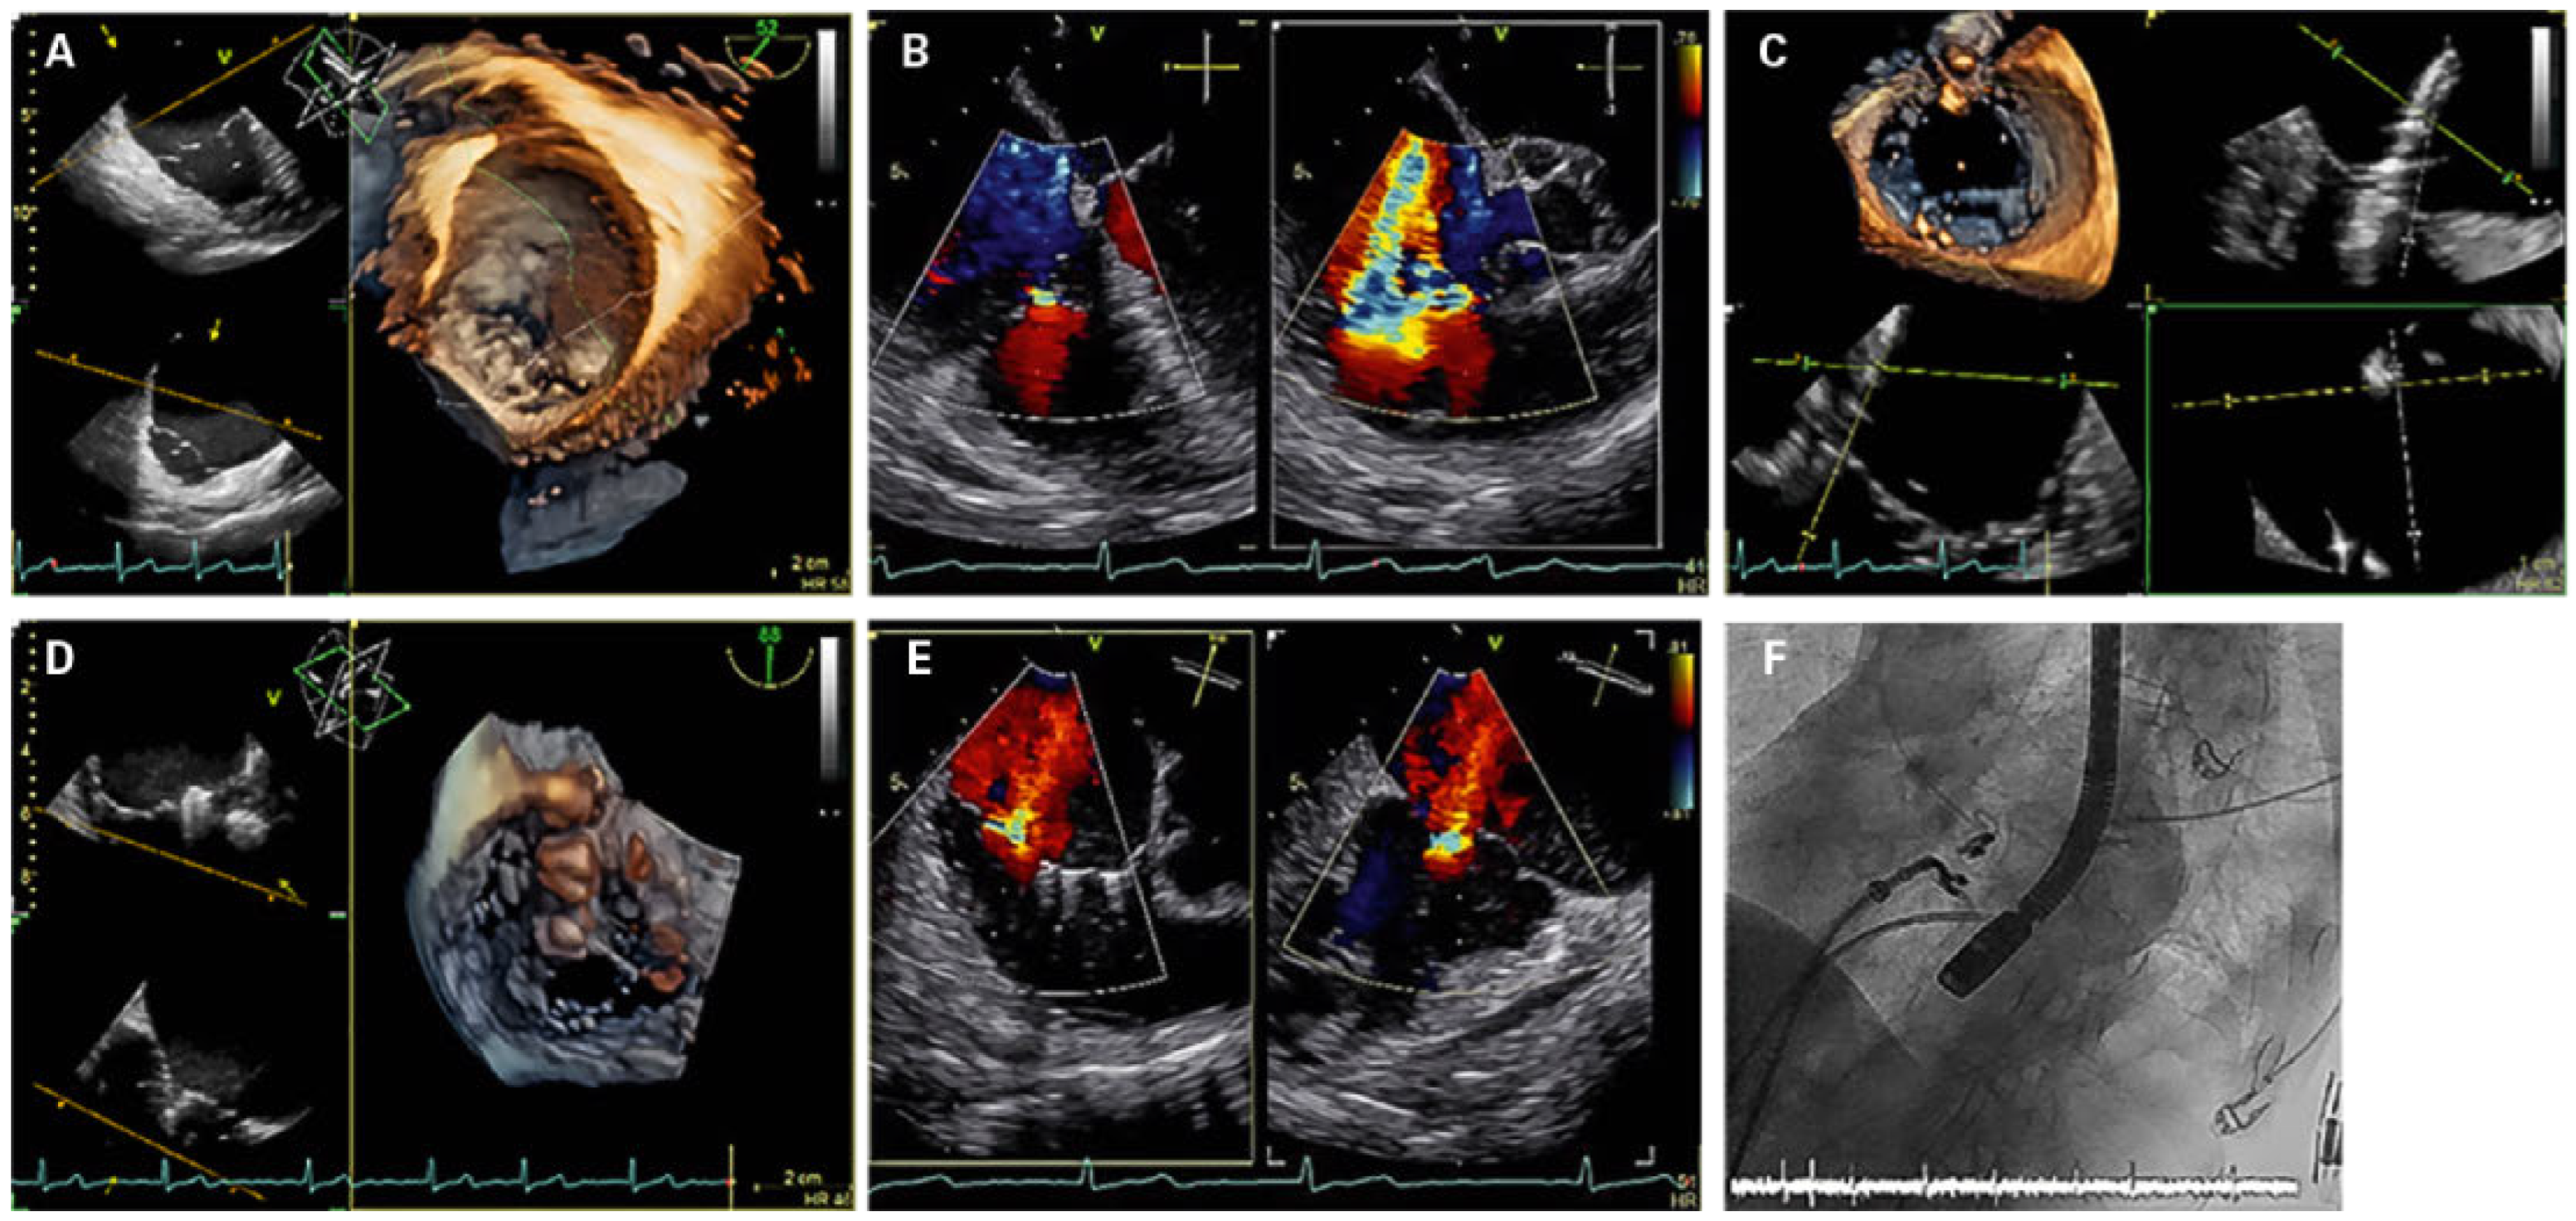

Cardioband at the tricuspid position